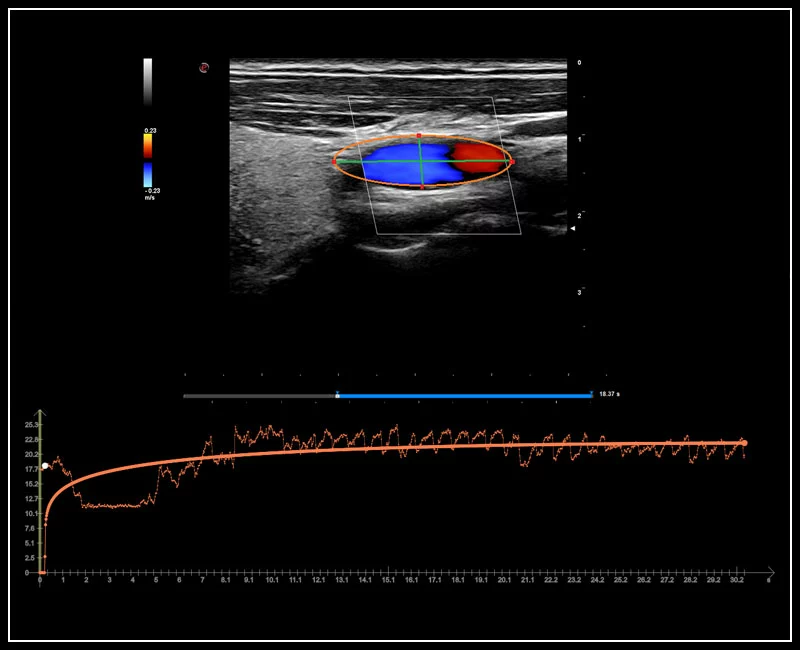

MyLab™9 Platform - QPack CnTI™ perfusion analysis post RF ablation

MyLab™9 Platform - QPack CnTI™ perfusion analysis post RF ablation